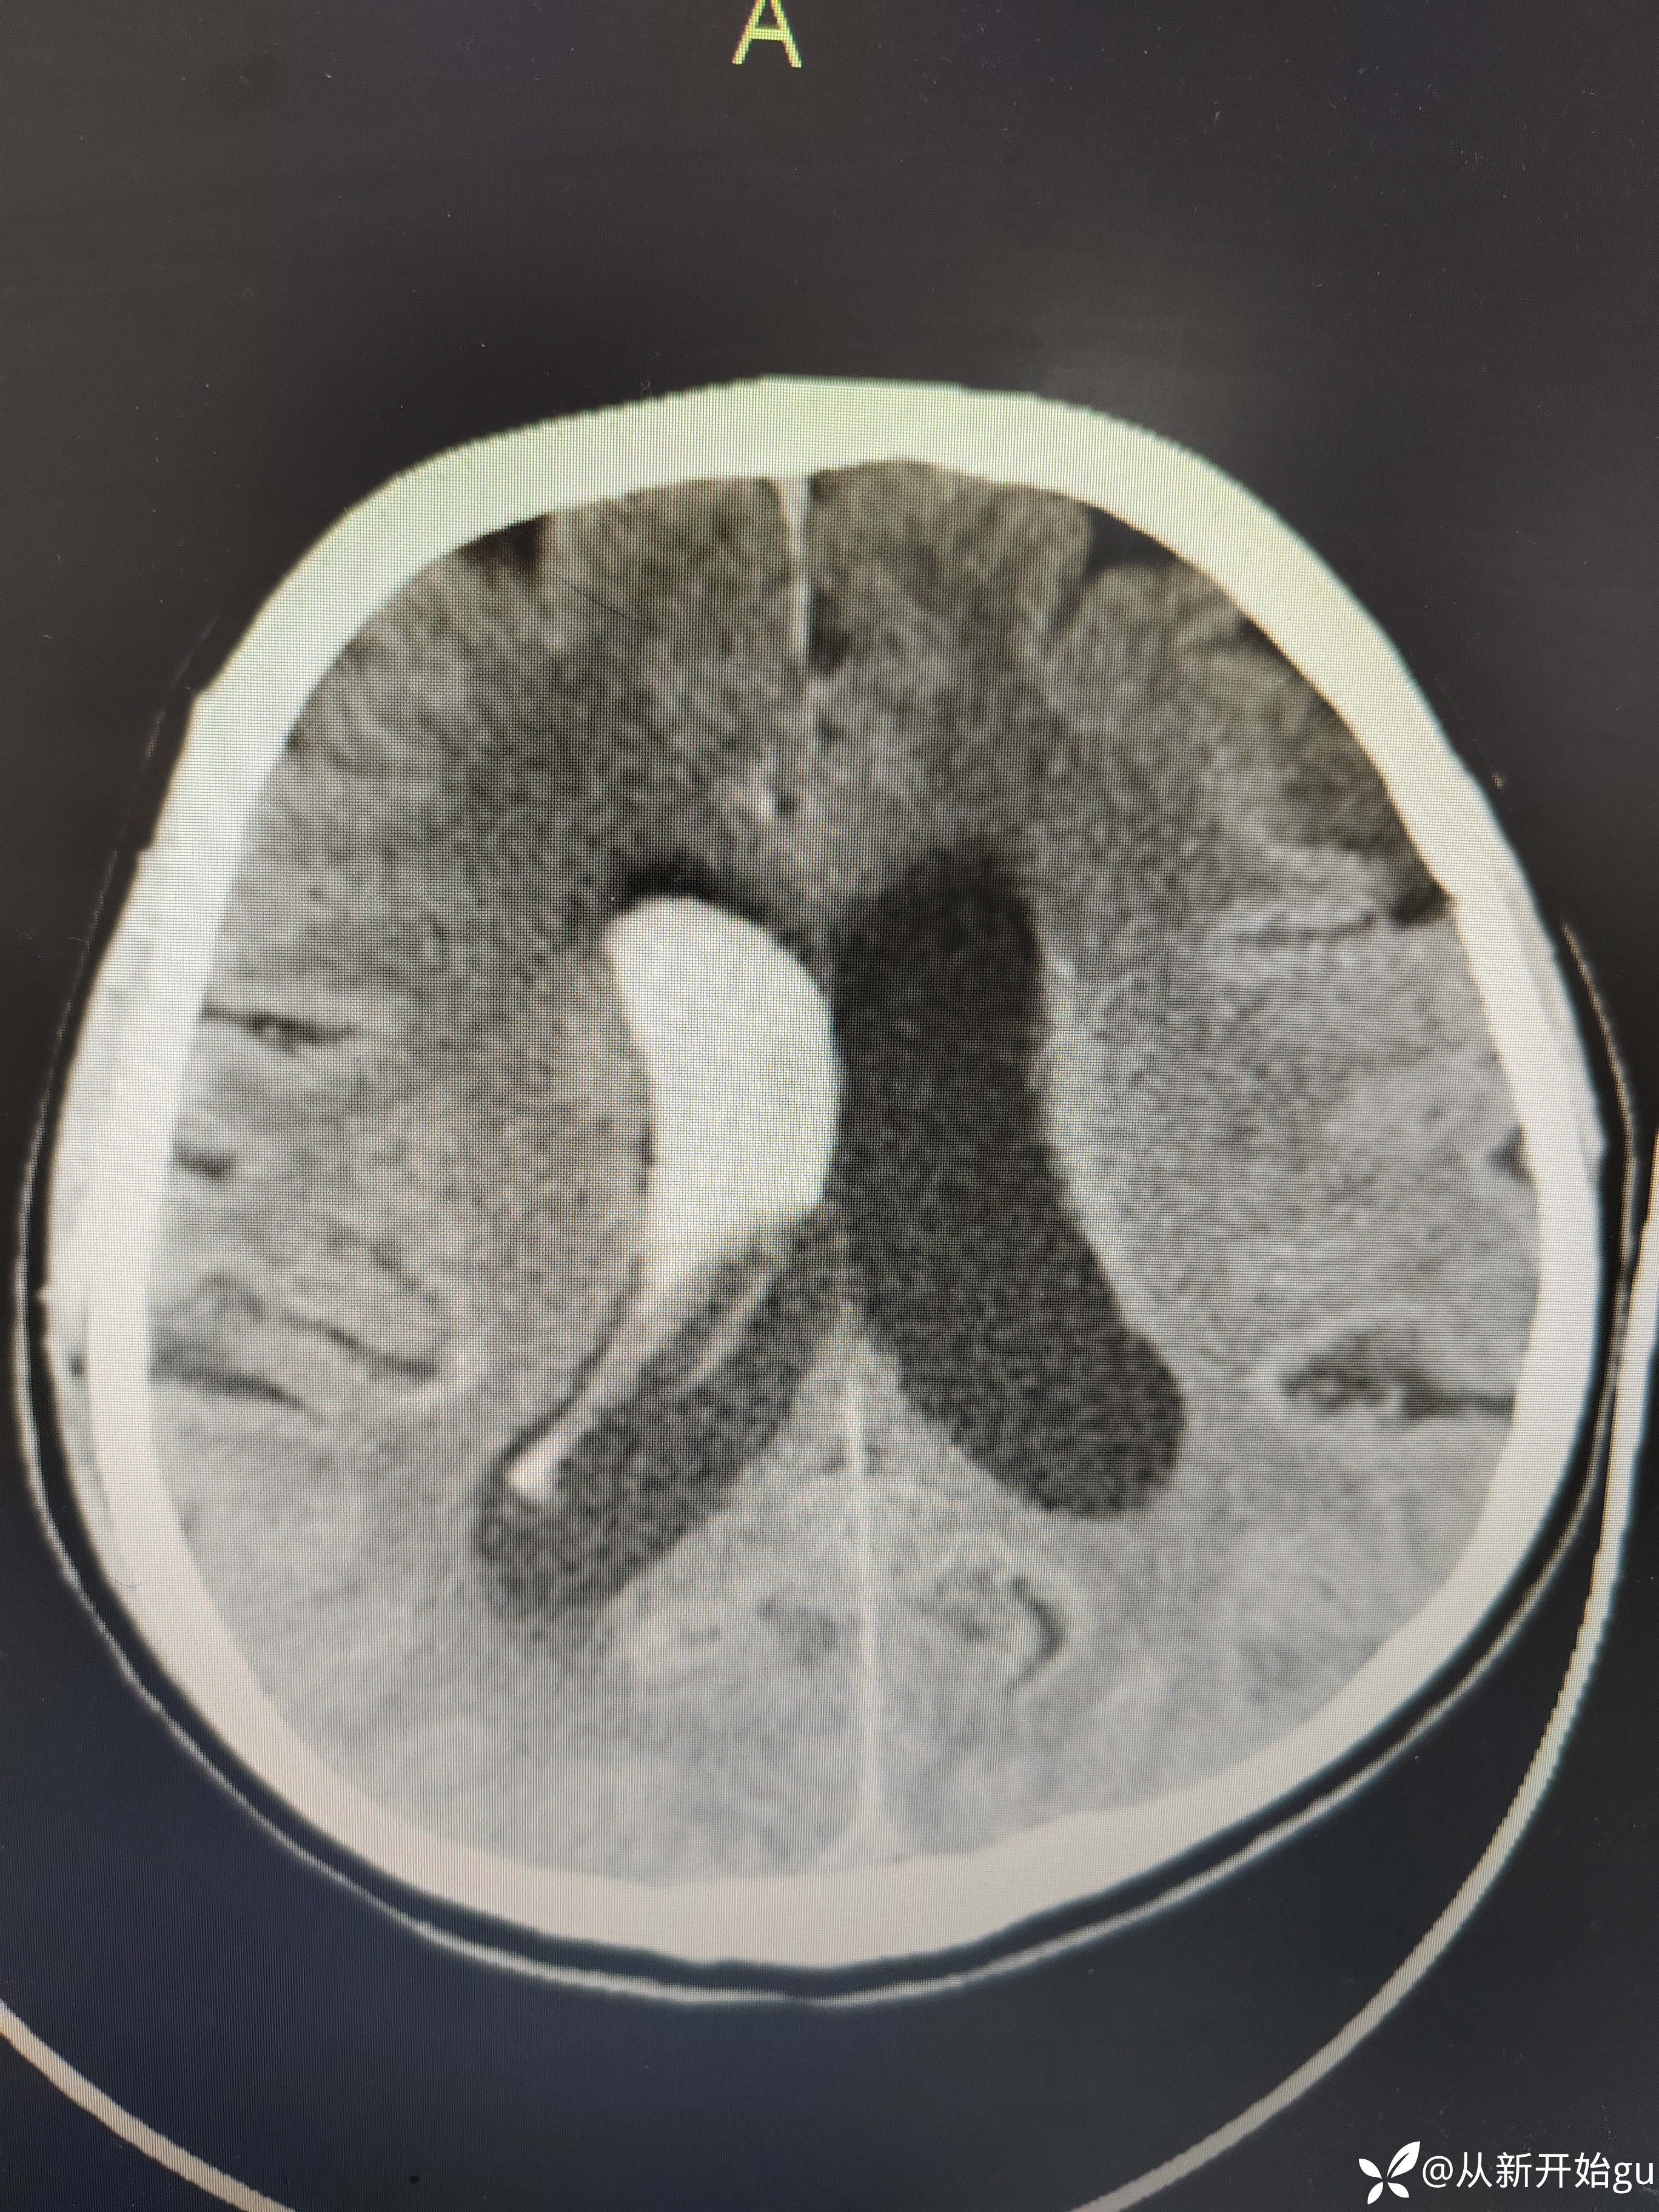

6天后颅脑CT.

6天后颅脑CT.